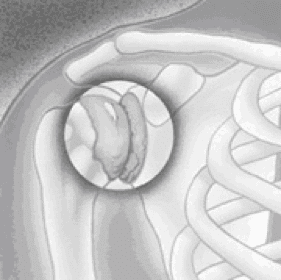

schouder arthrose

Arthrose

Arthrose is een proces van progressieve afbraak van kraakbeen.

Kraakbeen is een dunne, gladde en elastische structuur waarmee het gewricht bedekt wordt. Hierdoor kan een gewricht vlot en pijnloos bewegen.

Bij progressieve aantasting van dit kraakbeen onstaan er fissuren, afbrokkelingen en onregelmatigheden in deze structuur. Dit heeft een pijnlijke en stijf gewricht tot gevolg. In een verder stadium kunnen ook de omliggende pezen van de rotator cuff aangetast worden met nog meer functieverlies tot gevolg.

Indien de pijn of het functieverlies te ernstig zijn kan een schouderprothese een oplossing bieden.